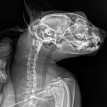

Сделали 3 рентгеновских снимка:

http://www.imageup.ru/img14/3262897/2019-01-18-pestrushka-01.jpg

На снимке сбоку врач изменений не обнаружил. Лёгкие отличные, позвоночник отличный, сердце чуть увеличенное, но для её возраста это норма. В желудке есть небольшие кусочки пищи.

http://www.imageup.ru/img14/3262898/2019-01-18-pestrushka-02.jpg

http://www.imageup.ru/img14/3262899/2019-01-18-pestrushka-03.jpg

На снимке головного мозга кошки врач предположительно нашёл небольшие тёмные пятна справа (???), и сказал, что это расширенные сосуды по типу варикоза и они давят на мозг, в результате чего животное бьётся в судорогах. Но это неточно и нужны консультация ветеринара-невропатолога и МРТ головного мозга кошки.